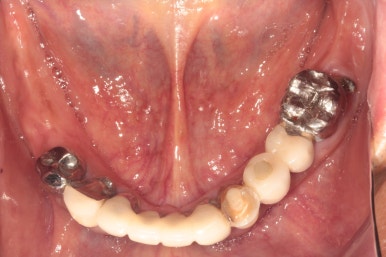

대부분의 어금니를 뽑고나서, 약 2달 후 구강내 사진입니다.

당연히 살릴 수 있는 치아는 모두 살립니다만, 애매한 치아를 남겨둘 경우 식사를 할 때 반대쪽 임플란트와 맞닿는 힘을 견딜 수 없습니다.

그래서 이번 50대 남자 환자분 같은 경우, 심한 만성치주염에 시달려 흔들흔들한 치아들은 모두 제거했습니다.

앞니만 남게 되었습니다...

위는 총 6개의 앞니가, 아래는 총 5개의 앞니가 남았습니다.

이를 뽑고 임시 틀니를 사용하시면서 2달 정도 기다리시게 되면, 위에 보시는 것과 같이 어느 정도 단단해진 잇몸이 생기게 됩니다.

단단한 잇몸이 생겨 이를 뺀 자리를 막아주어야 잇몸뼈 이식술을 충실하게 해낼 수 있습니다.

심한 만성치주염을 앓고 계신 분들이 쉽게 이를 빼면서 바로 임플란트 심기를 원하시는데... 세상에 요행은 별로 없습니다... 뼈이식 많이 해야하는 케이스는 이렇게 적어도 2달 이상 기다리셔야만 한답니다.